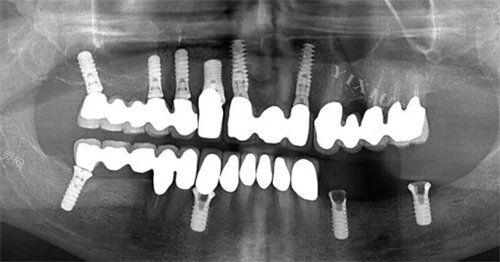

李显军 - 种植专科医师,亚非牙科骡马市店院长,拥有十余年种植经验,完成种植病例超万例,擅长全口种植修复、上颌窦内外提升等高难度种植手术。

肖慧 - 从事口腔临床工作近二十年,擅长美学区种植修复、复杂牙列缺损种植修复、前牙小创口智能化美齿美白技术及牙周手术治疗。

赵云飞 - 十余年临床经验,专注于缺失牙种植修复、全瓷牙及贴面美学修复,擅长即刻种植、上颌窦提升等手术。